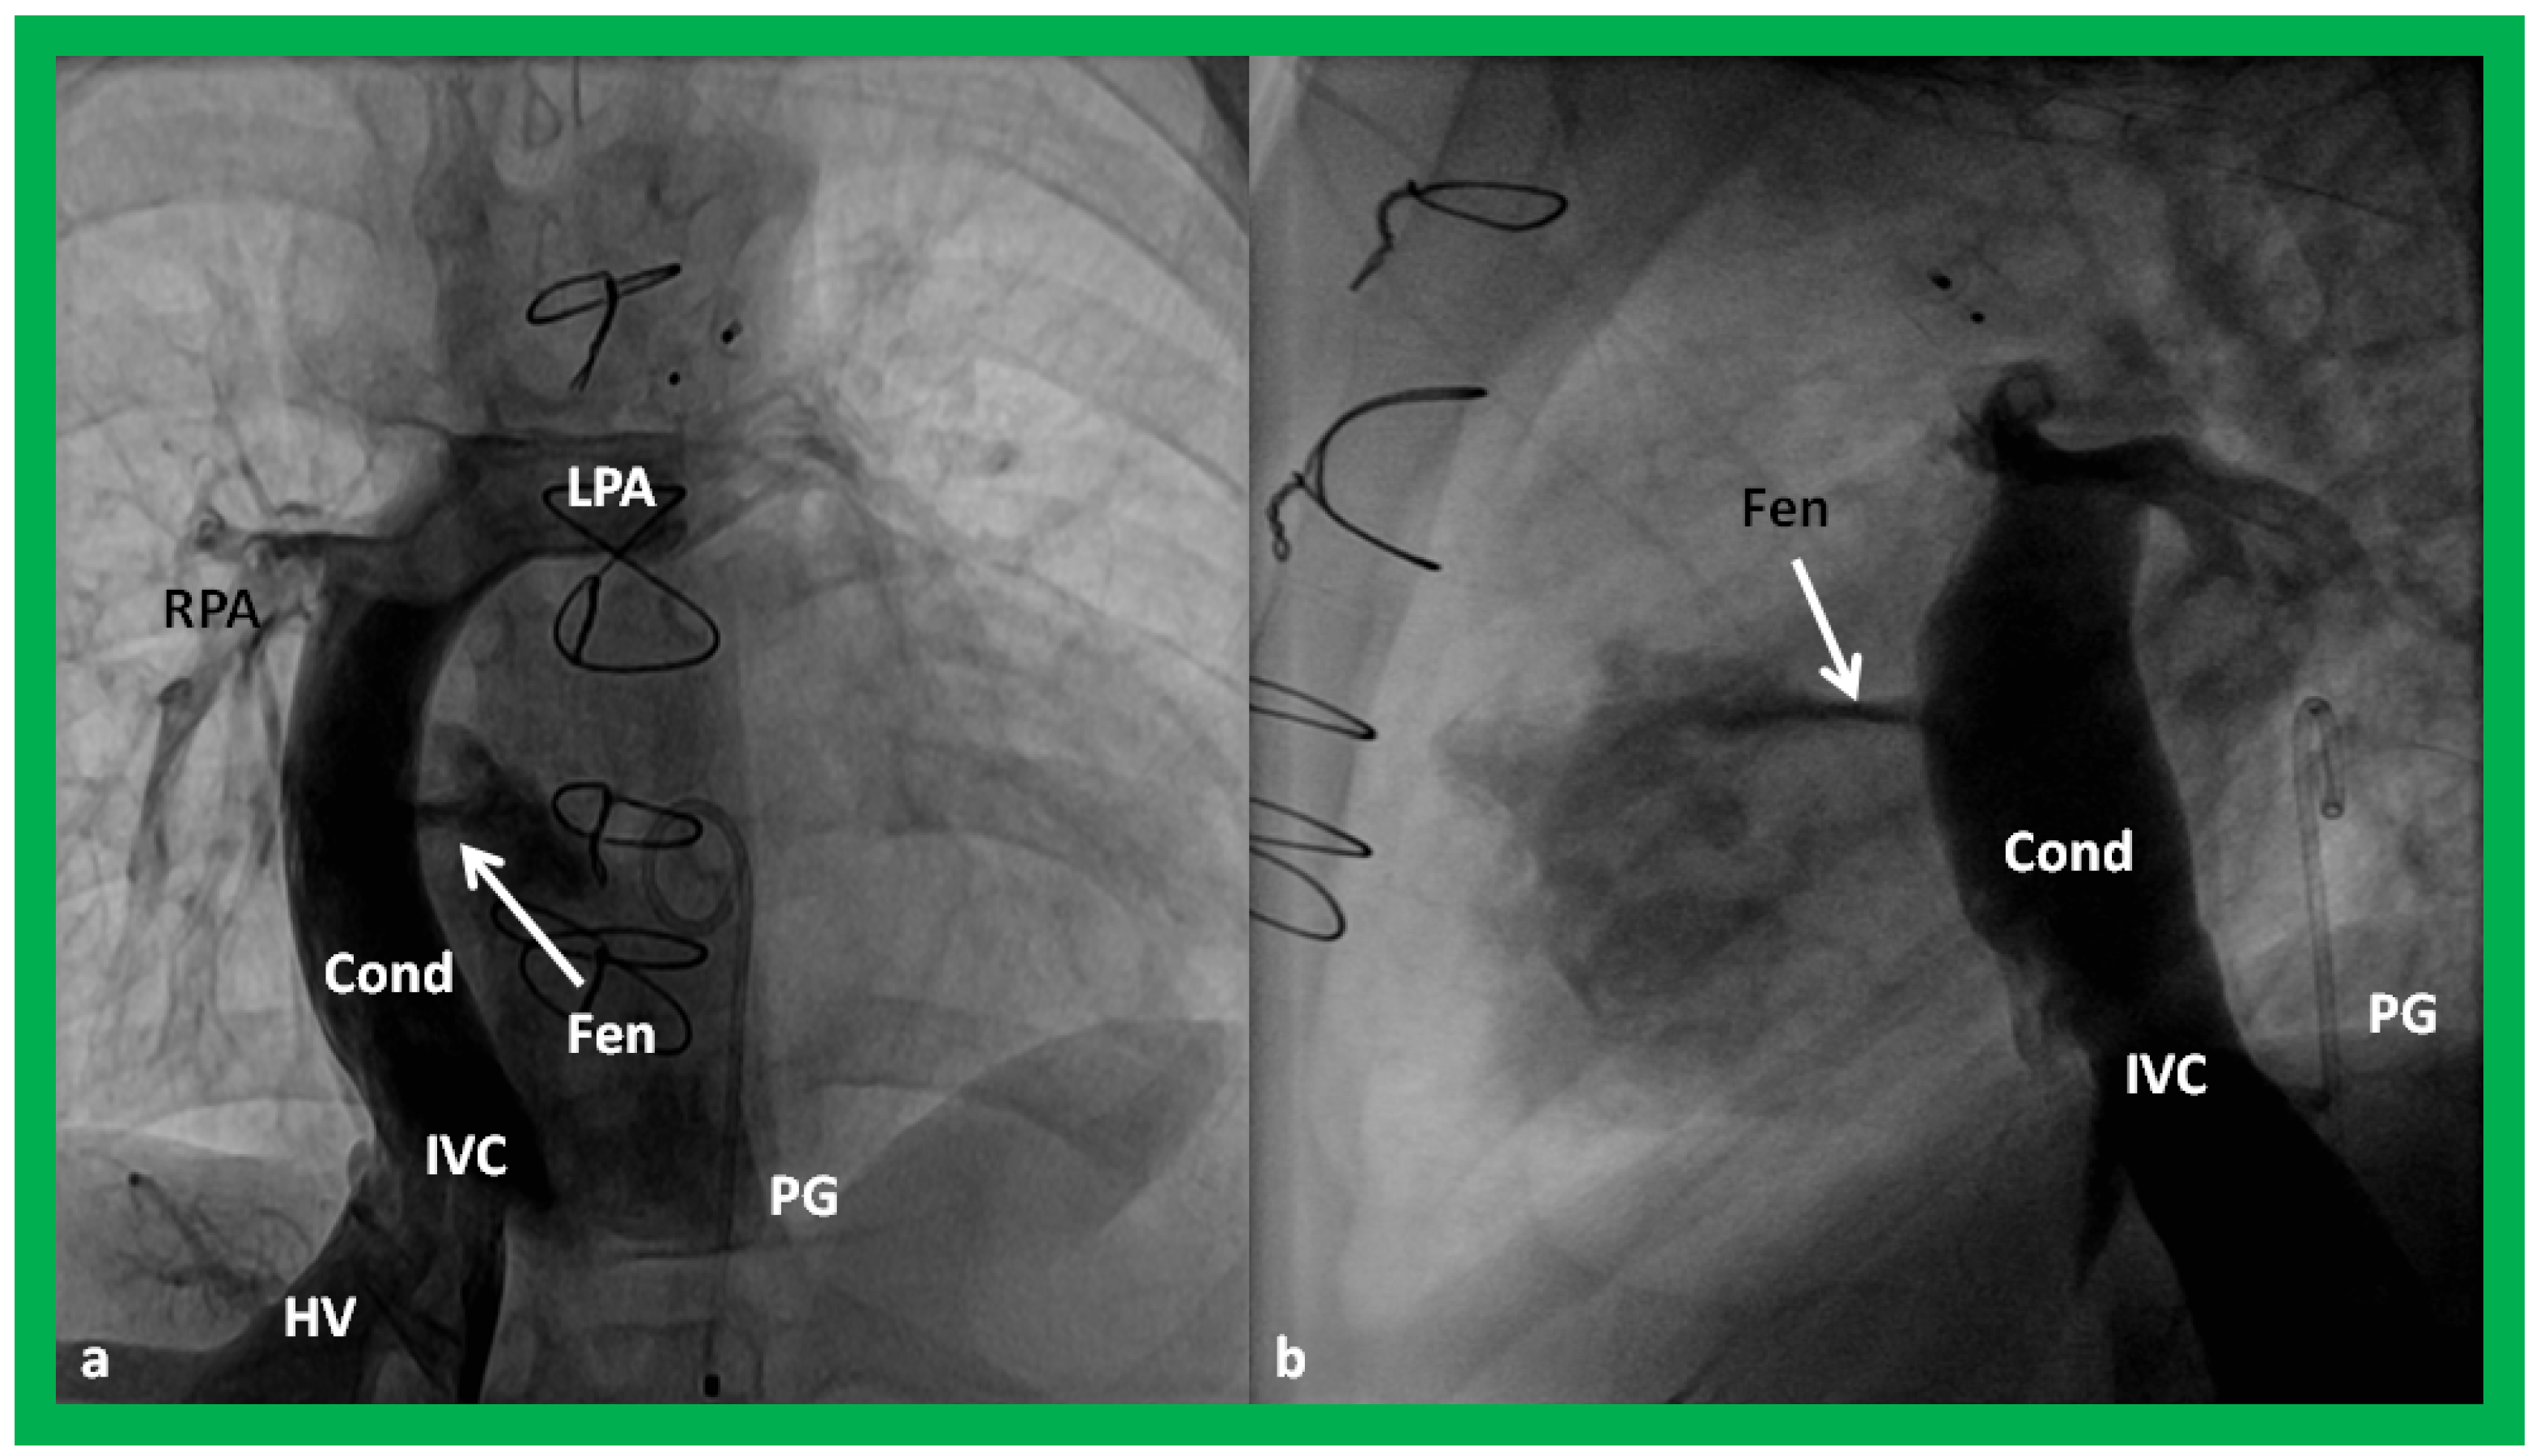

Surgically created fenestrations (Figure 50, Figure 51, Figure 52 and Figure 53) can also be demonstrated by color Doppler studies and the mean gradient across the fenestration (Figure 52 and Figure 53) is helpful in determining the physiologic state; a mean gradient of 4 to 8 mmHg is considered adequate.

Angiographic counter part of the Fontan conduit with fenestration is shown, in Figure 54, to have better comprehension of the anatomy of the Fontan.

Figure 24. Selected cine frames in postero–anterior (a) and lateral (b) views, demonstrating a Blalock–Taussig (BT) shunt (arrow in a) to care for infants with decreased pulmonary blood flow (a) and pulmonary artery banding (PB) (arrow in (b)) in babies with increased pulmonary blood flow (b), respectively, during Stage I of Fontan procedure. C, catheter; LPA, left pulmonary artery; RPA, right pulmonary artery. Neonates with adequate pulmonary blood flow do not need any intervention and can go directly to Stage II at about the age of 3 months. Reproduced from Rao PS, Indian J Pediatr 2015;82:1147–1156 [36].